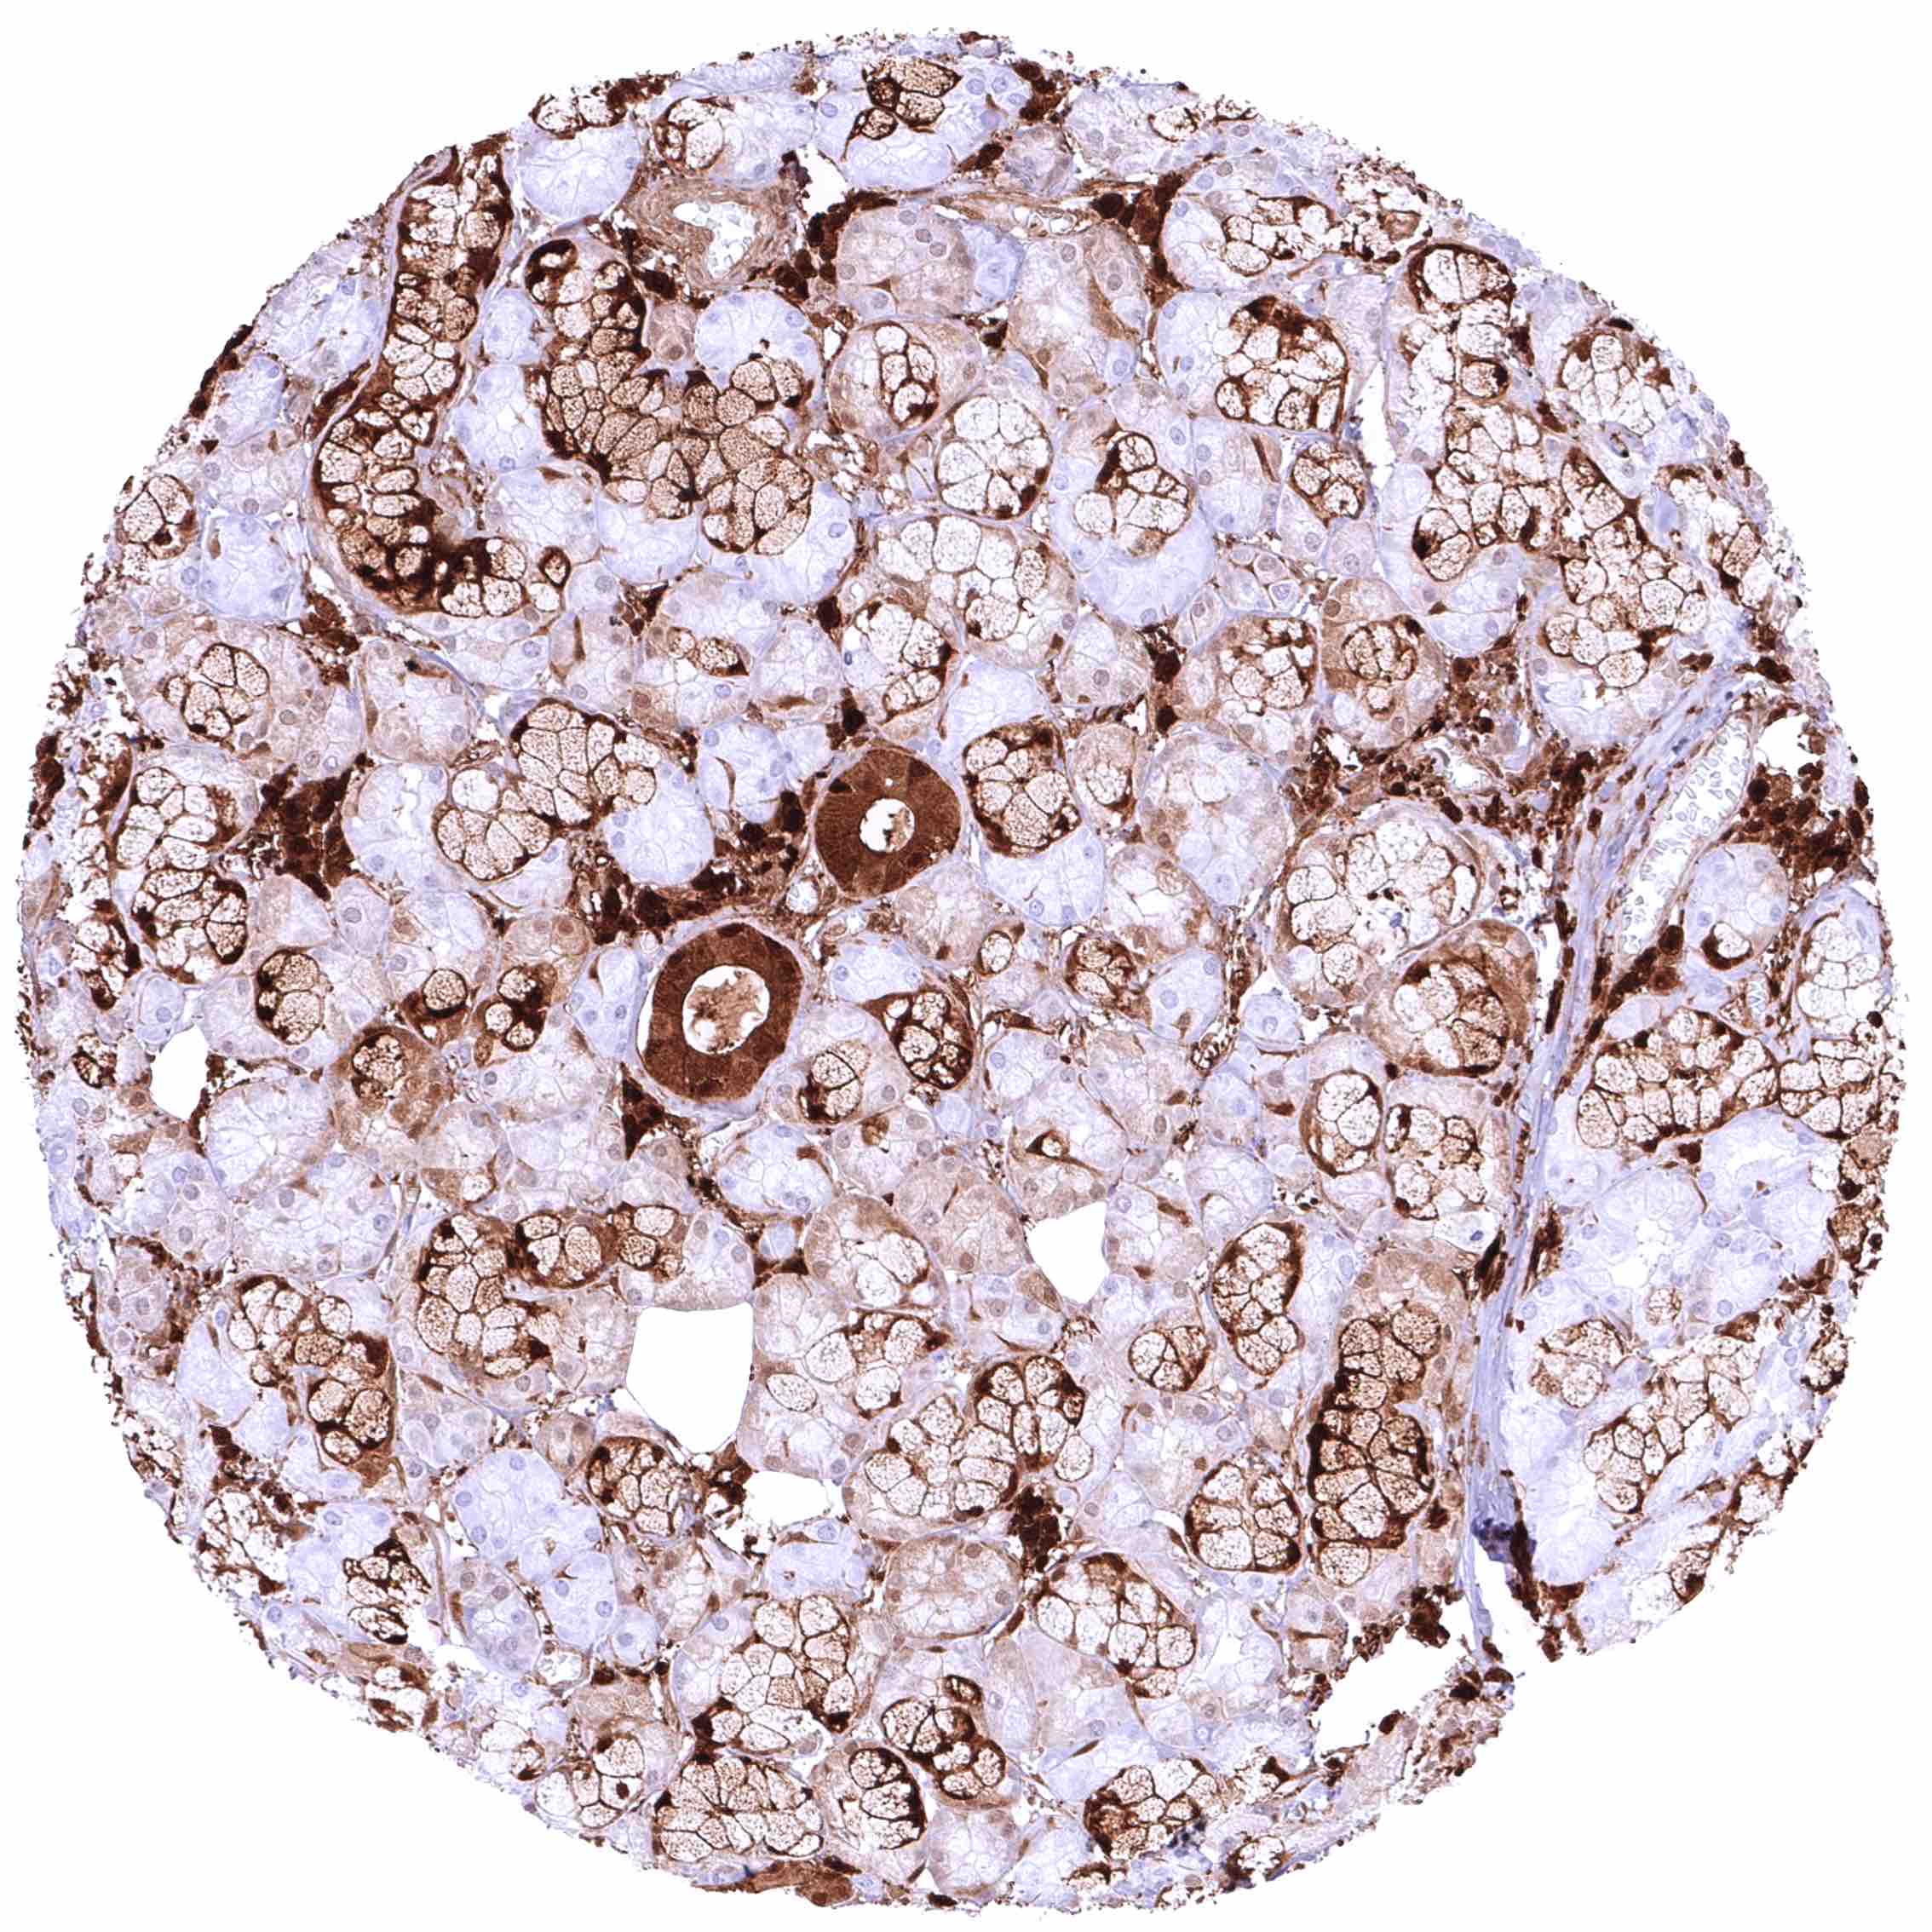

Bone marrow – Moderate to strong, nuclear and cytoplasmic GSTP1 staining of most cell populations although some cell types (erythropoiesis_) remain GSTP1 negative